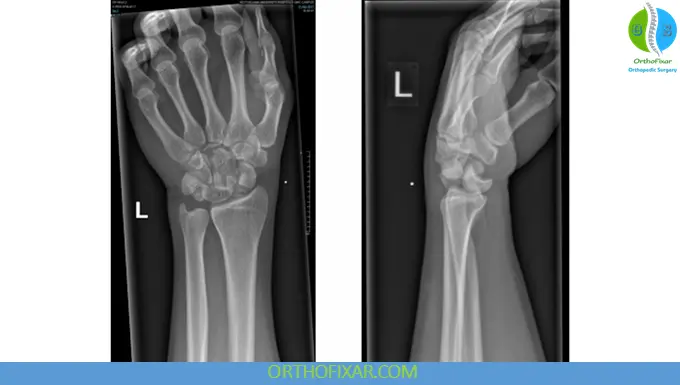

Radiographic Evaluation

Standard Imaging

- PA view

- Lateral view (most important)

- Oblique view

Key Radiologic Signs

PA View:

- Disrupted Gilula lines

- Scapholunate gap > 3 mm (“Terry Thomas sign”)

- Triangular (“piece-of-pie”) lunate appearance

Lateral View:

- Misalignment of capitate and lunate

- “Spilled teacup sign” → indicates volar lunate dislocation